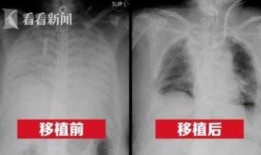

港媒最新爆料新冠肺病人,新冠肺病患者真实生活与康复历程”

最近港媒可是爆出了一个大新闻,让人不禁瞪大了眼睛!说的是新冠肺病人的一些最新情况,听起来是不是有点刺激?那就跟着我一起,来揭开这...